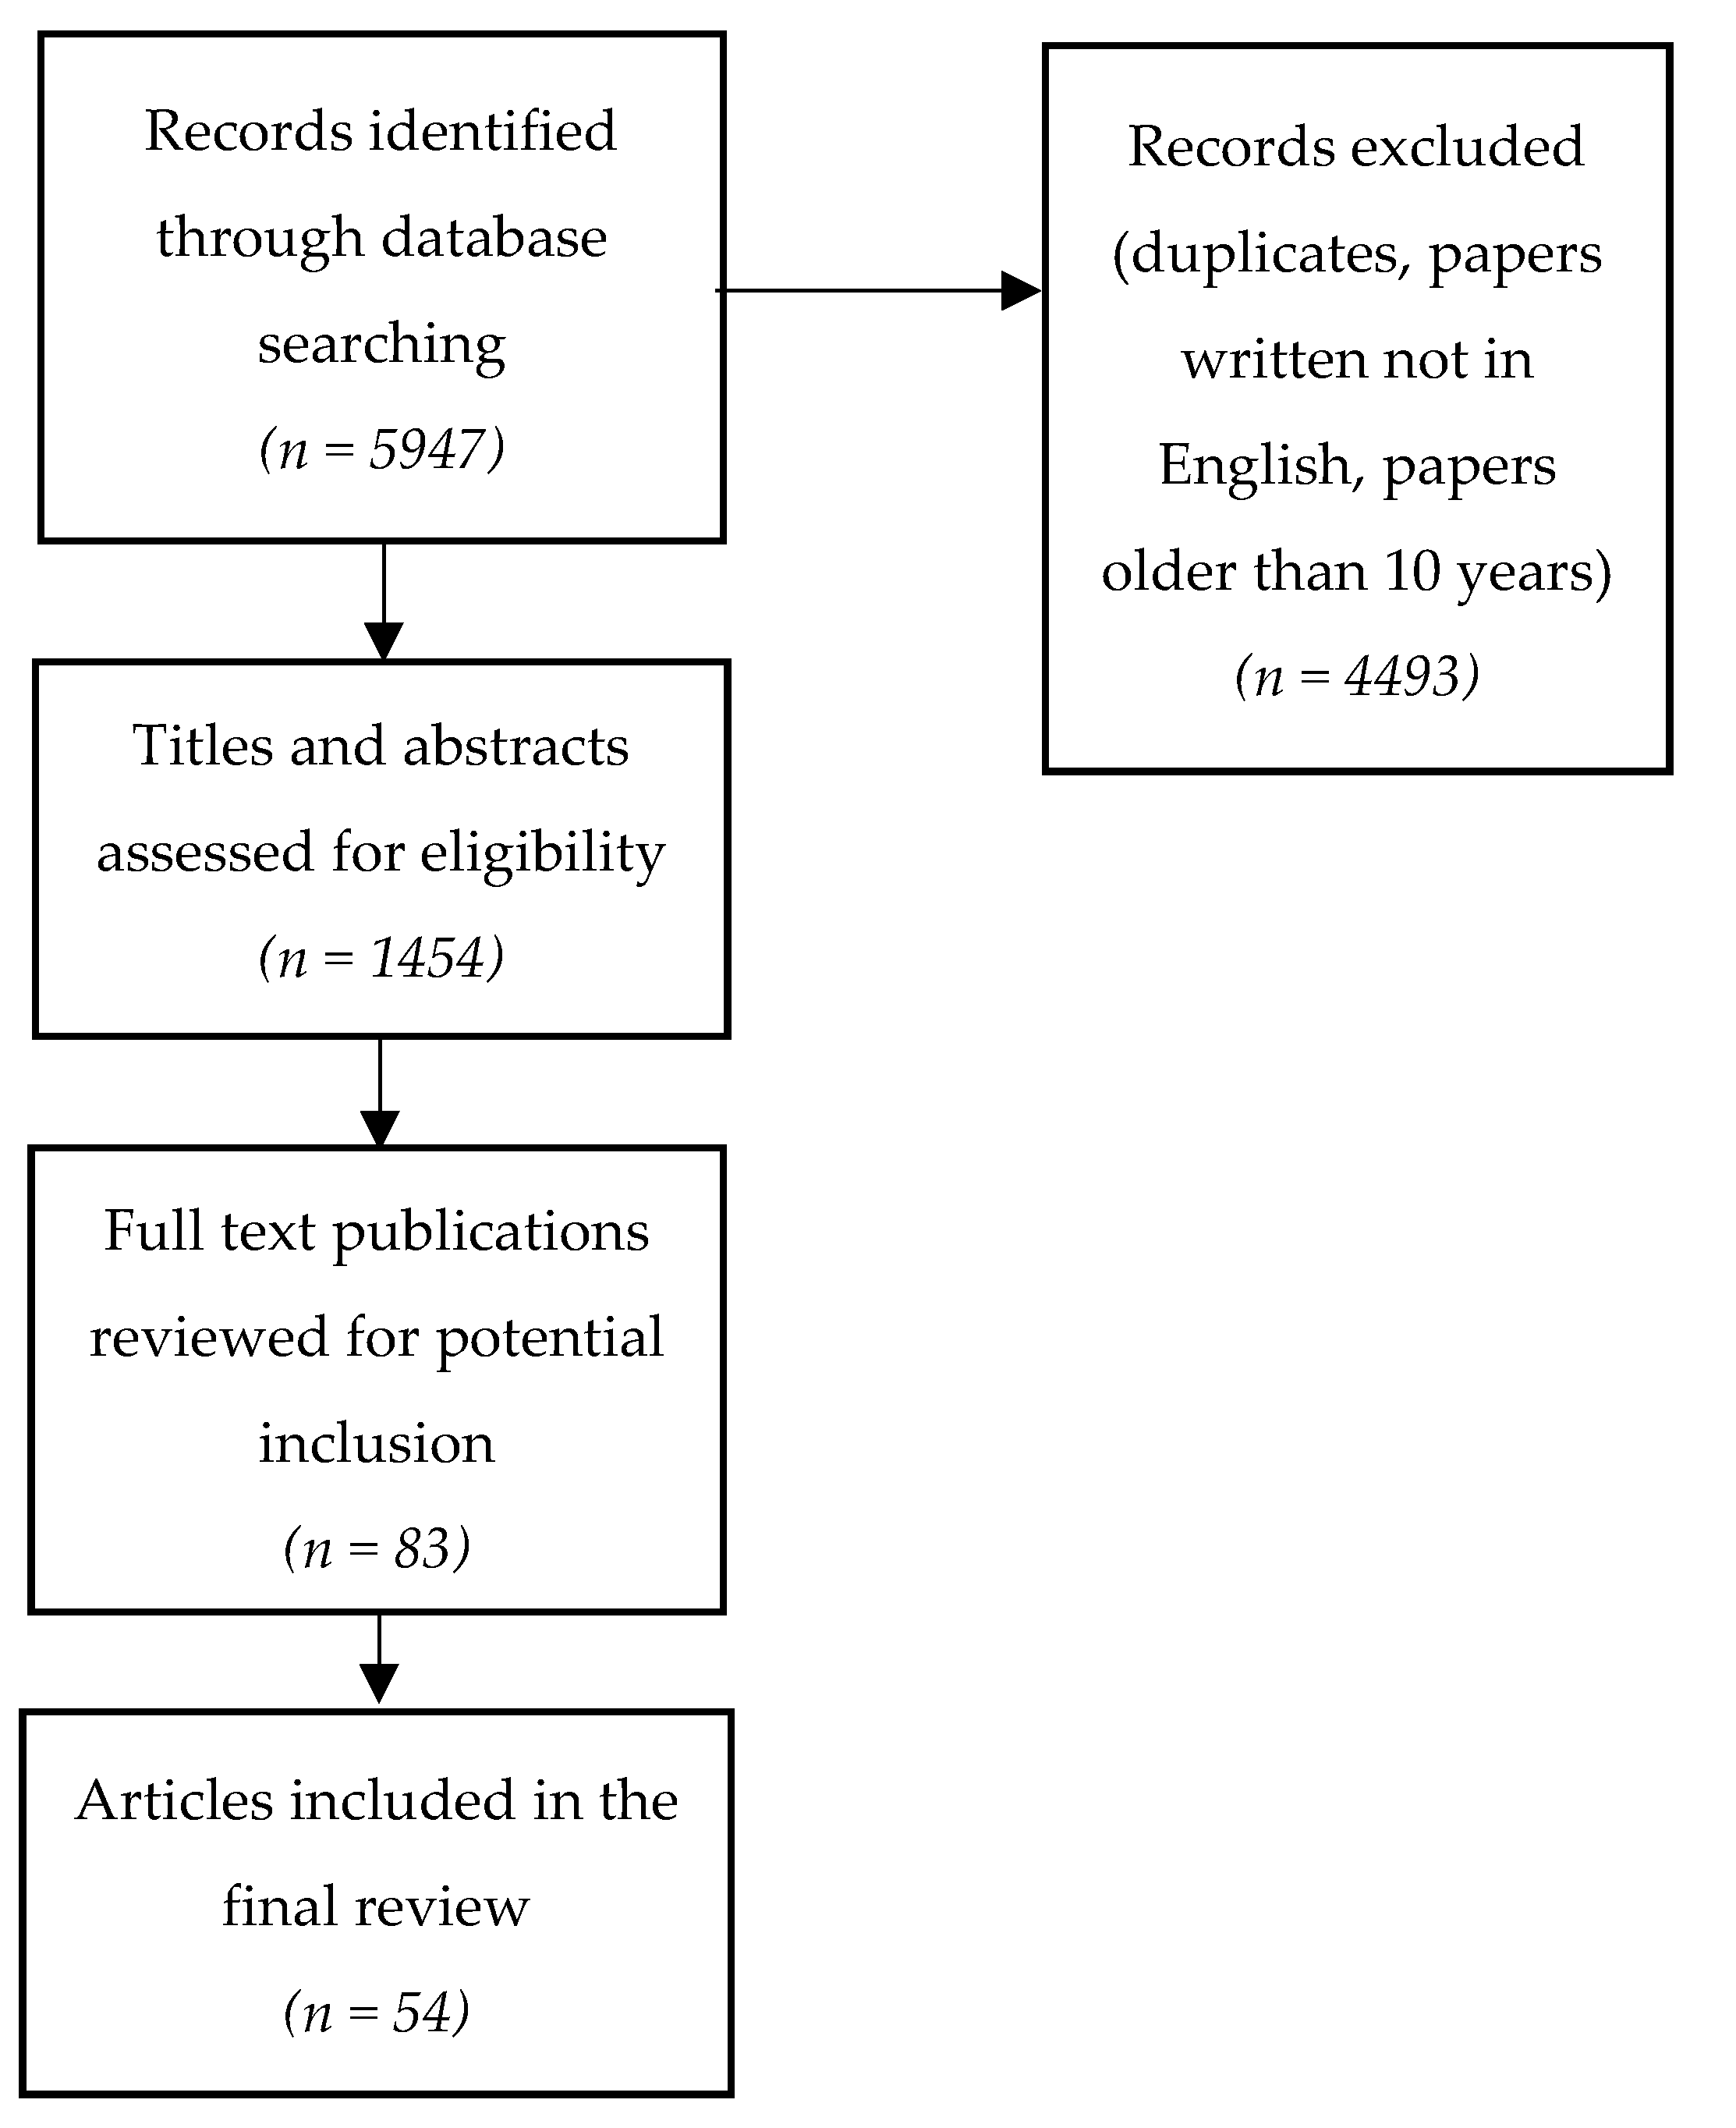

2. Literature Search and Synthesis